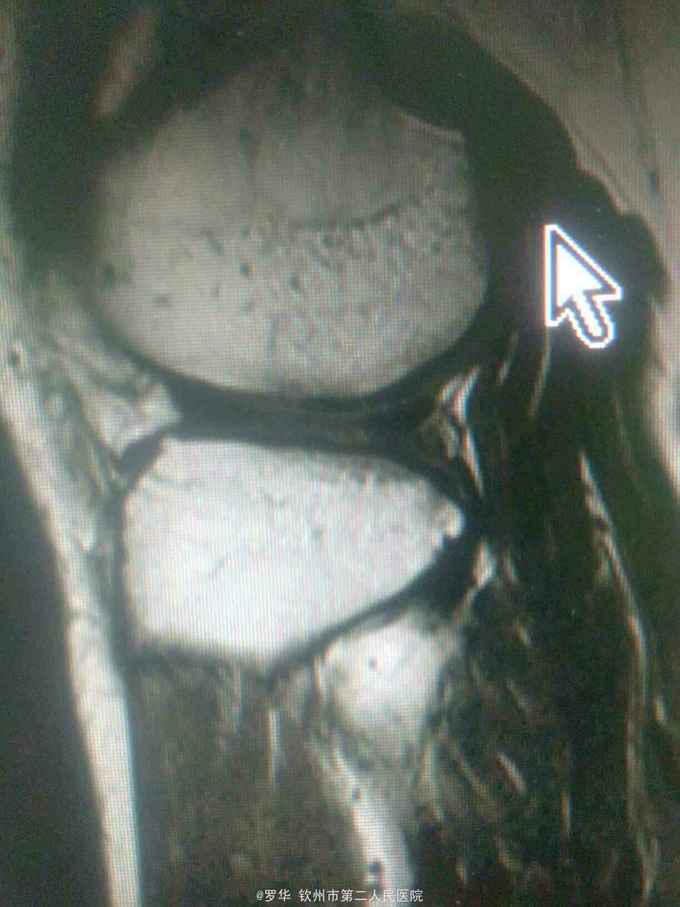

主诉:扭伤致左膝关节活动受限3月余。病史:患者男性,31岁,于入院3月余前扭伤左膝关节,致左膝关节肿痛、活动受限,尚可站立行走,但不能剧烈运动及重体力劳动,曾行磁共振检查提示左膝前交叉韧带损伤,半月板损伤,现为进上一步治疗入院。

查体:左膝关节无明显压痛,前抽屉试验阳性,侧方应力试验、麦氏征、研磨试验均阴性,膝关节屈伸活动可,余查体未见特殊。 辅查:膝关节磁共振提示左前交叉韧带损伤,左膝关节半月板损伤。

诊断:左膝关节前交叉韧带断裂,左膝关节半月板损伤。 治疗:予硬外麻下行左膝关节前交叉韧带重建术。